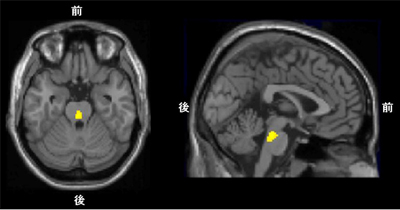

次に被験者に、脳内のセロトニントランスポーターの密度を検討できる[11C]DASBという薬剤を用いてPET検査を受けてもらいました。不公平な提案の拒否率とセロトニントランスポーターの密度との関係を調べたところ、背側縫線核を含む中脳のセロトニントランスポーターの密度が低い人ほど、実直で正直で他人を信頼しやすい性格傾向にあり(図2)、かつ、不公平な提案の拒否率が高いことがわかりました(図3、 4)。つまり、中脳のセロトニントランスポーターの密度が低い人は、坊っちゃんのような実直な性格で、その結果、不公平な提案をされた時に、義憤に駆られ、自分の利得を台無しにしてまで、拒否行動(報復行動)に出る傾向があることが示されました。

1. 図4 図3の関係が認められた背側縫線核を含む中脳部分(黄色)。